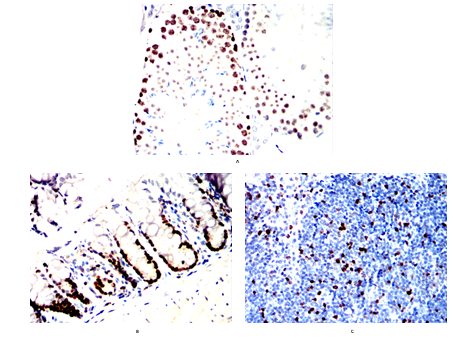

分类: 科研抗体货号: 20354别名: KIA; Ki-67; MKI67应用: IHC,IF反应种属: Human,Mouse,Rat,Rabbit,Monkey